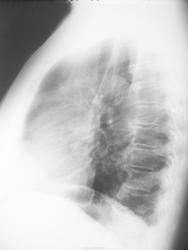

Сегодняшние снимки

img_2738.jpgimg_2739.jpg

Миргалина wrote:

Ну, а Вы боялись. Так есть динамика, а? Так-то, друзья!

Дисковидный ателектаз расправился, инфильтрации как не было, так и нет.